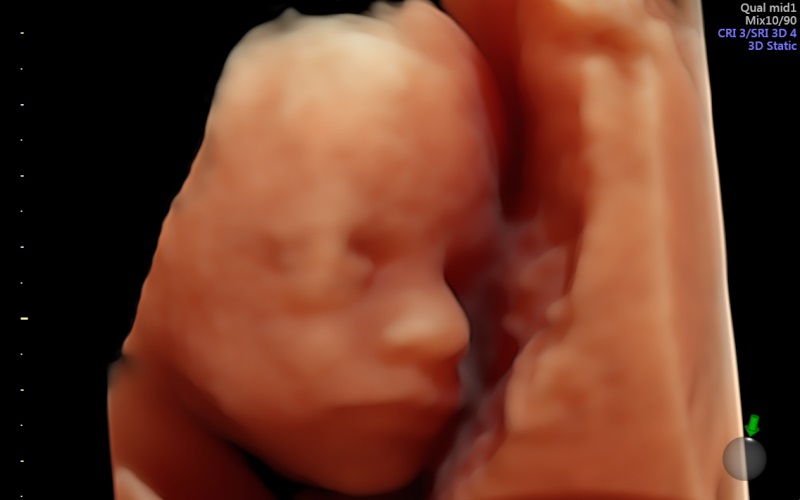

¿Qué es una ecografía en 4D?

Ventajas de realizar la ecografía en cuatro dimensiones y en qué semana del embarazo se recomienda

Todas las familias están deseando conocer la carita de su futuro bebé, y hoy en día muchas madres recurren a las ecografías en 4D, que ofrecen imágenes realmente impresionantes. A quién no se le ha caído la baba ante esas pantallas que nos muestran al feto como si ya estuviera fuera… Pero, ¿sabemos en qué consiste ...

Un nuevo ecógrafo 3D/4D muestra imágenes más nítidas

Se trata un equipo de alta gama especializado en aplicaciones obstétricas

Desde que aparecieron las primeras ecografías en 4D el mundo de la obstetricia se revolucionó por completo. Y es que, más allá de las implicaciones diagnósticas que pueda tener esta prueba, para una madre, desde el punto de vista psicológic...